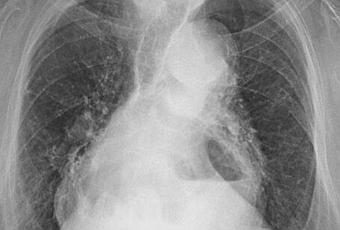

PA DE TORAX (TELE DE TORAX)

LA PROYECCION RADIOLOGICA OBTENIDA NOS MUESTRA LOS SIGUIENTES HALLAZGOS:

-Vía aérea permeable, tráquea con desviación hacia la derecha por botón aórtico.

-Mediastino, con aumento de sus diámetros, a expensas de imagen de aparente topografía retro cardiaca con nivel hidro aéreo en su interior, que mide aproximadamente 7.2 X 6.5 cm.

-Corazón, con índice cardiotorácico de 0.58.

-Hilios pulmonares, con presencia de adenopatías, de predominio izquierdo.

-Trama bronco-vascular, conservada, con reforzamiento para hiliar.

-Ambos campos pulmonares, con opacidad reticular difusa bilateral. Con aparente atelectasia a nivel basal de pulmón derecho.

-Recesos cardiofrénicos y costofrénico sin alteraciones.

OPINIÓN RADIOLÓGICA:

EN EL PRESENTE ESTUDIO RADIOGRÁFICO, CON IMAGEN SUGERENTE DE HERNIA HIATAL CON ASCENSO DE CAVIDAD GÁSTRICA RETRO CARDIACA VS ABSCESO PULMONAR. SE SUGIERE REALIZAR PROYECCIÓN LATERAL PARÁ MEJOR CARACTERIZACIÓN.

DATOS DE NEUMOPATÍA INTERSTICIAL CRÓNICA.

ATEROESCLEROSIS.

CARDIOMEGALIA GRADO II.